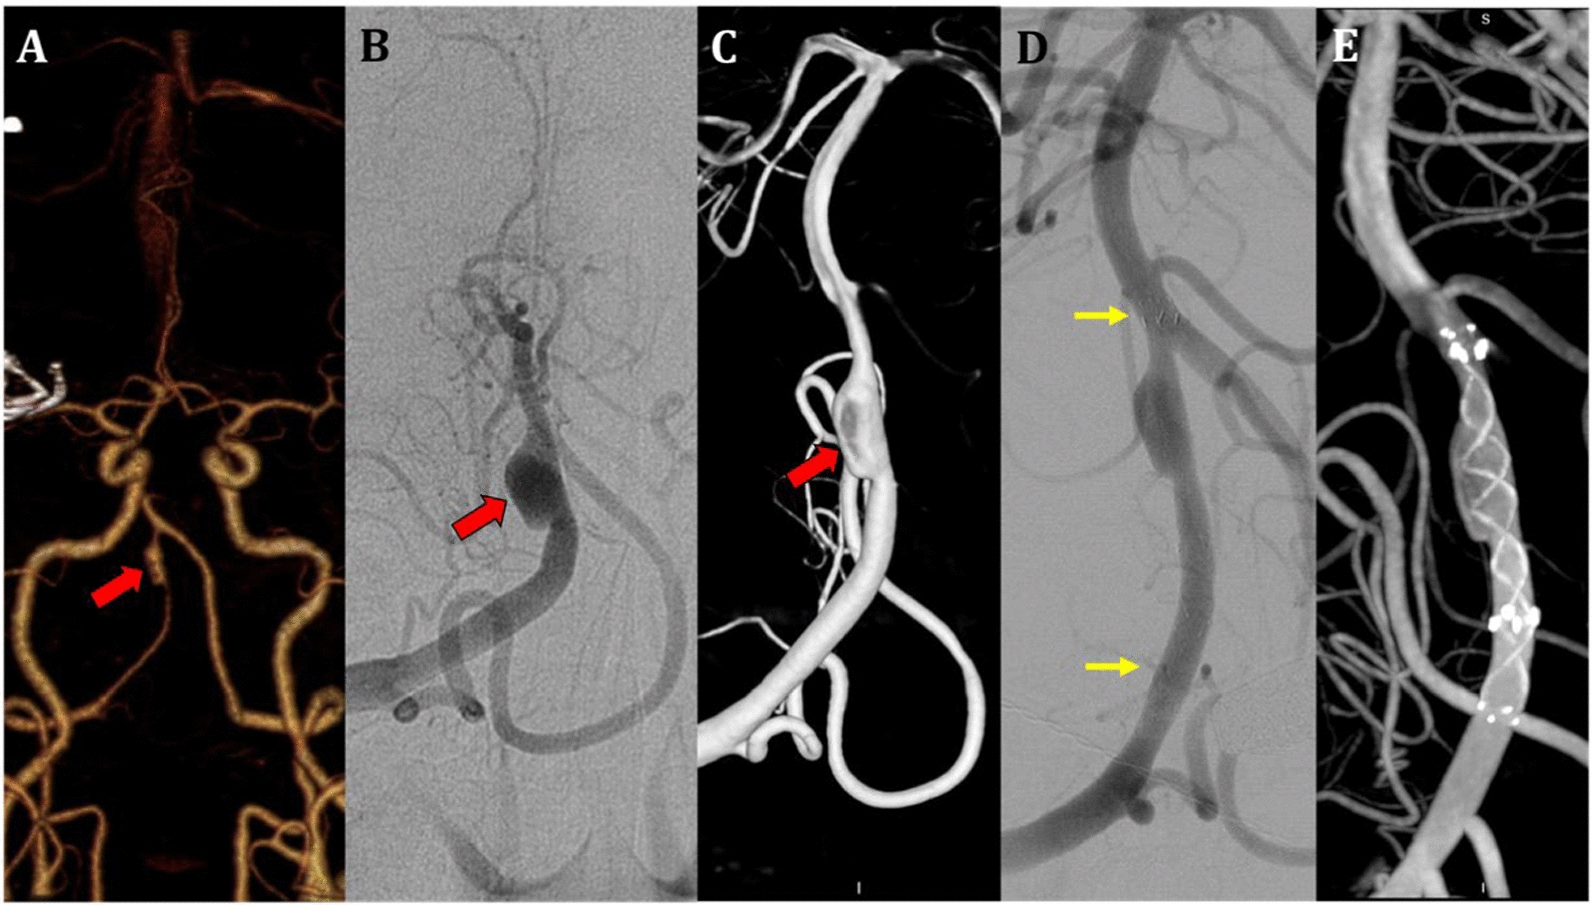

Recently, endovascular treatment (EVT) has emerged as a choice for VAD management due to its good efficacy, and low periprocedural morbidity. Endovascular procedures are performed when an ischemic stroke caused by VAD does not respond to AT medical treatment, there is stenosis or occlusion, or there is subarachnoid haemorrhage. Endovascular procedures such as stent angioplasty, double stent, stent-assisted coil and microvascular brain surgery (bypass) must be carried out promptly. According to a research study, the technique used to perform an EVT procedure for a VAD is determined by every fundamental condition of the case to be treated, as well as factors such as the patient's clinical symptoms, hemodynamic status, collateralization of the cerebral blood vessels, particularly the posterior circulation area, and significant features of the anatomy of blood vessels and perforators. If a VAD ruptures, the EVT procedure aims to close the ruptured area either by completely closing the VA or by performing stent-assist coiling. Meanwhile, for VADs that have not ruptured, the main aim of EVT is to ensure that the hemodynamic flow of cerebral blood is maintained using stenting. The choice of EVT treatment depends on the patency of the contralateral vertebral artery (VA) and the relationship between the dissection segment and the location of the origin of the posterior inferior cerebellar artery (PICA). Complete occlusion of the dissection segment is the best option. If the dissection is proximal or distal to the PICA without hypoplasia of the contralateral VA, treatment can be carried out with total occlusion of the dissection segment with a coil, where the PICA will obtain flow from the contralateral VA. If the VAD is present at the PICA branch, isolation of the dissected segment can be done by coil trapping with PICA revascularization via bypass surgery or PICA stenting [22, 23, 24]. The management therapy of EVT with stenting, and coil embolization or double stenting is shown in Figs. 4 and 5.

Fig. 5

A Case of Vertebral Artery Dissection treated with EVT (Double Stent). An asymptomatic 62-year-old man, smoker ( +), history of hypertension ( +) and history of SAH. From 3D-MRA and C-DSA Neuroimaging shown: A. 3D-MRA showed a dissecting aneurysm with fusiform dilatation at the right vertebra artery, segment V4; B. C-DSA showed a dissecting aneurysm with fusiform dilatation at the right vertebra artery from AP view; C. C-DSA showed a dissecting aneurysm with fusiform dilatation at the right vertebra artery from Lateral view of C-DSA Roadmap; D/E. Post-EVT procedures showed that a double stent was inserted inside the lumen of the right VA (The yellow arrow shows the placement of a double stent inside the VAD fusiform dilatation aneurysm)